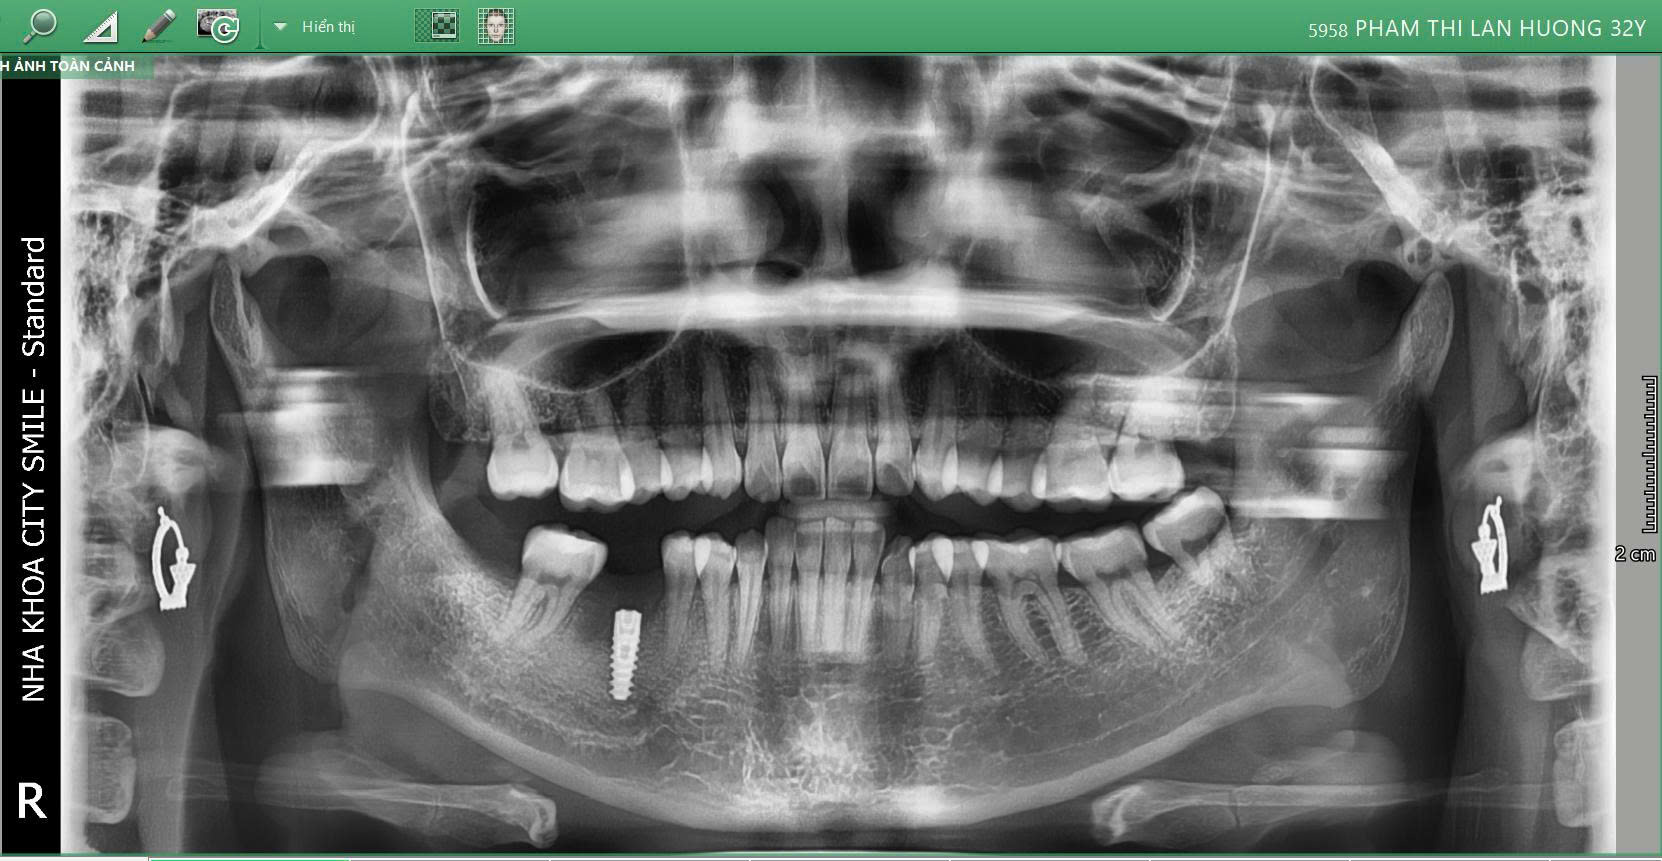

Phác đồ điều trị tại City Smiles

Cắm trụ Implant ETK Pháp: trụ Implant tích hợp xương tốt, độ bền cao, phù hợp cả người trẻ và trung niên

Quy trình vô trùng chuẩn y khoa: giảm tối đa rủi ro và biến chứng

Theo dõi sát quá trình tích hợp trụ Implant: đảm bảo kết quả ổn định lâu dài

Kết quả

Sau cấy ghép, răng 46 được khôi phục ổn định, giúp chị Lan Hương ăn nhai dễ dàng hơn, nụ cười tự nhiên và tăng sự tự tin trong giao tiếp.